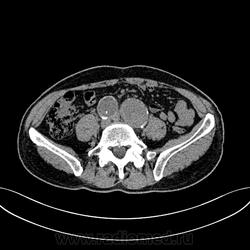

Пациент лежит в кардиологии. Прислали на аортографию. 2 врача УЗИ несколько разошлись в диагнозах: одна видит тромбированную аневризму брюшной аорты, другая - тромбоз нижней полой вены.

А мы получили вот такие красивые картинки.

Шикарно! Тромбированная аневризма инфраренального отдела (над бифуркацией), бифуркации и общих подвздошных артерий, синдром Лериша справа.

И еще маленькая аневризмочка наружной подвздошной слева. Честно говоря, меня больше всего впечатлили коллатерали, благодаря которым клинически он вообще не соответствует исследованию. Конечности теплые, пульсация слабая, но как-то прослеживается...